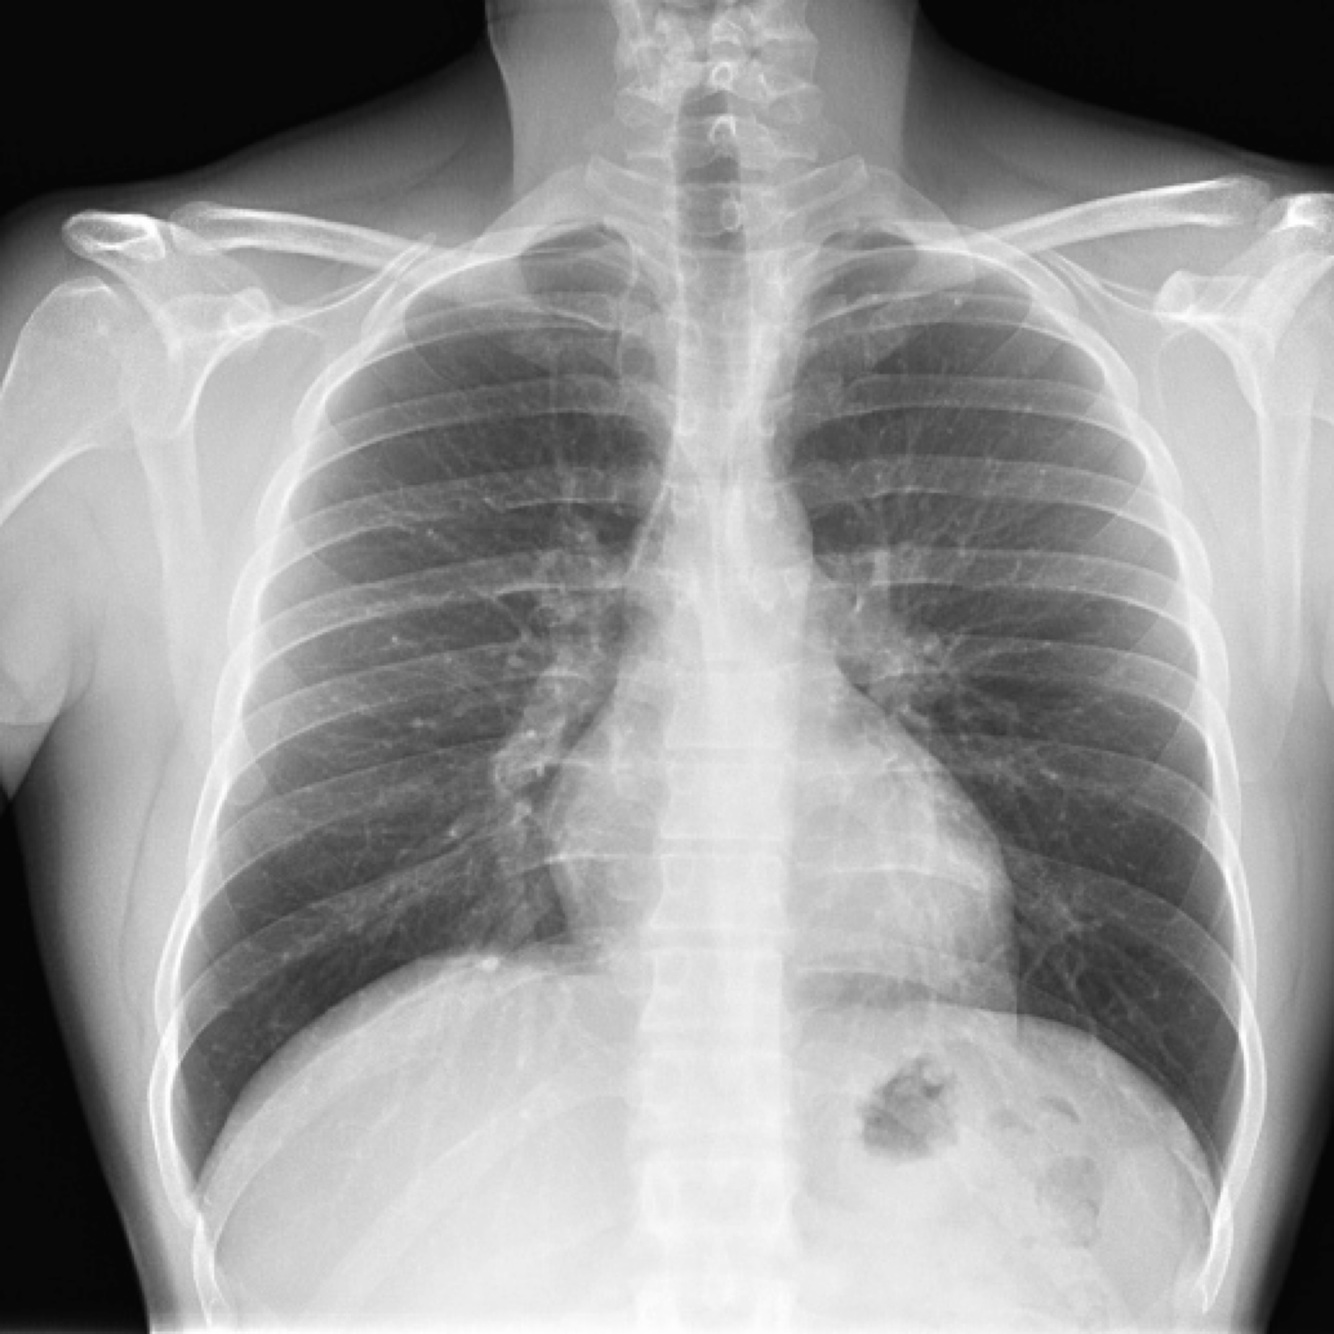

Dx

Neumotorax en pulmón derecho